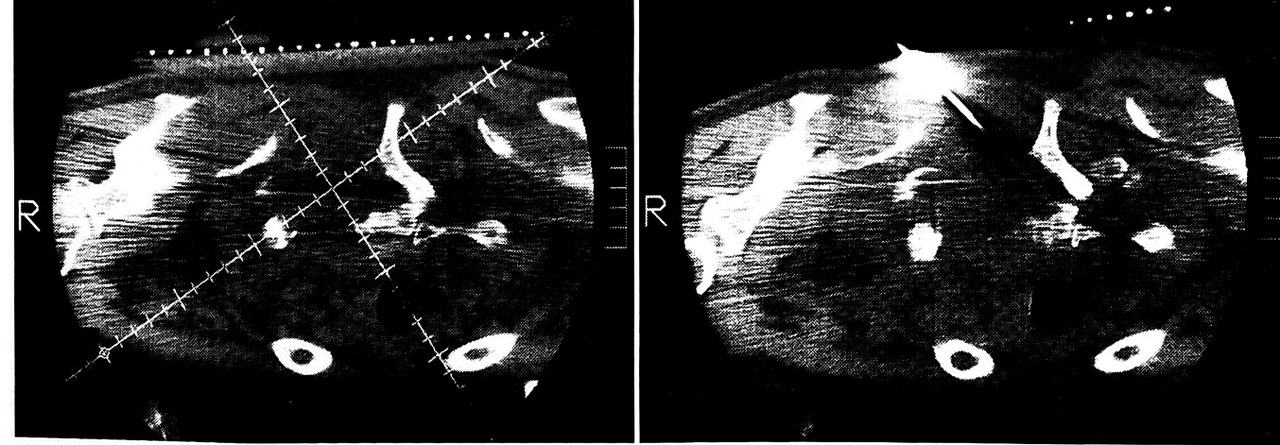

Рис 6. Больной К. Неспецифический воспалительный процесс в дне левой вертлужной впадины с формированием абсцесса в малом тазе. a — диагностическое компьютерное сканирование; б — введение контрастного вещества с целью дифференциальной диагностики.